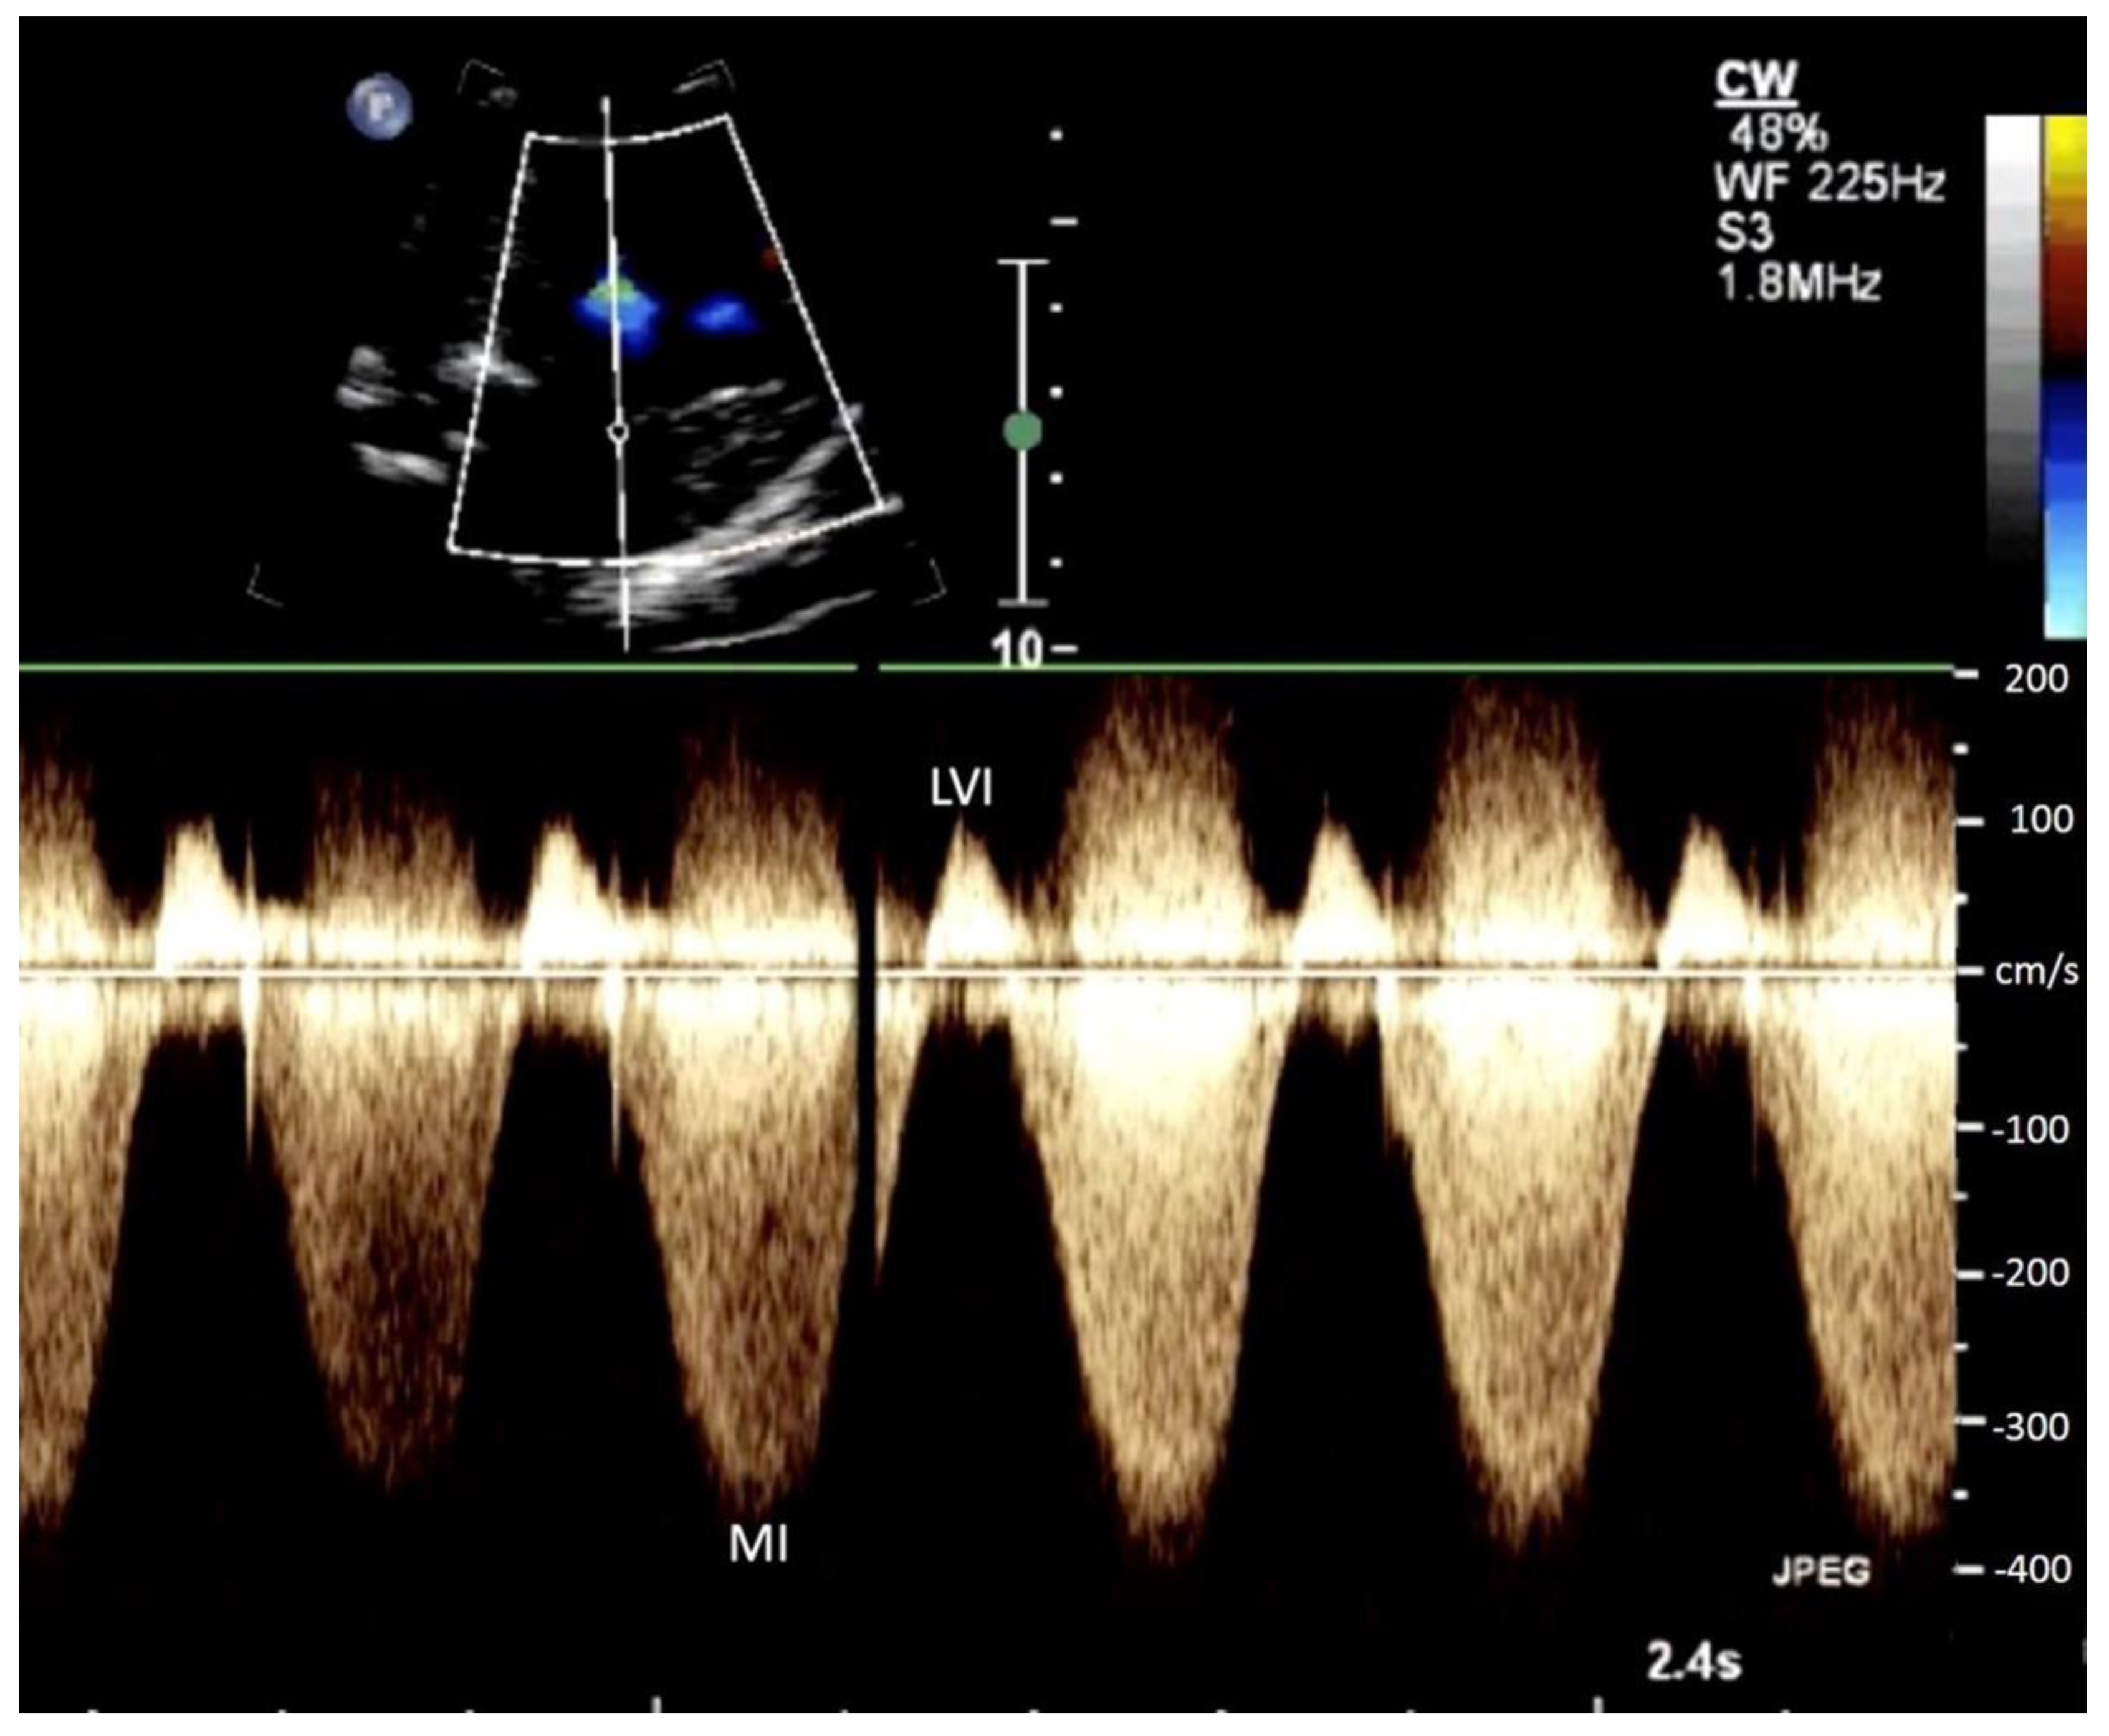

2.2. Procedure

2.3. Outcome

| MR Vmax (cm/s) | 379.61 (±76.11) | 390.91 (±58.55) | 359.29 (±99.94) | 1.01 (0.99–1.02) | 0.385 | 0.407 |